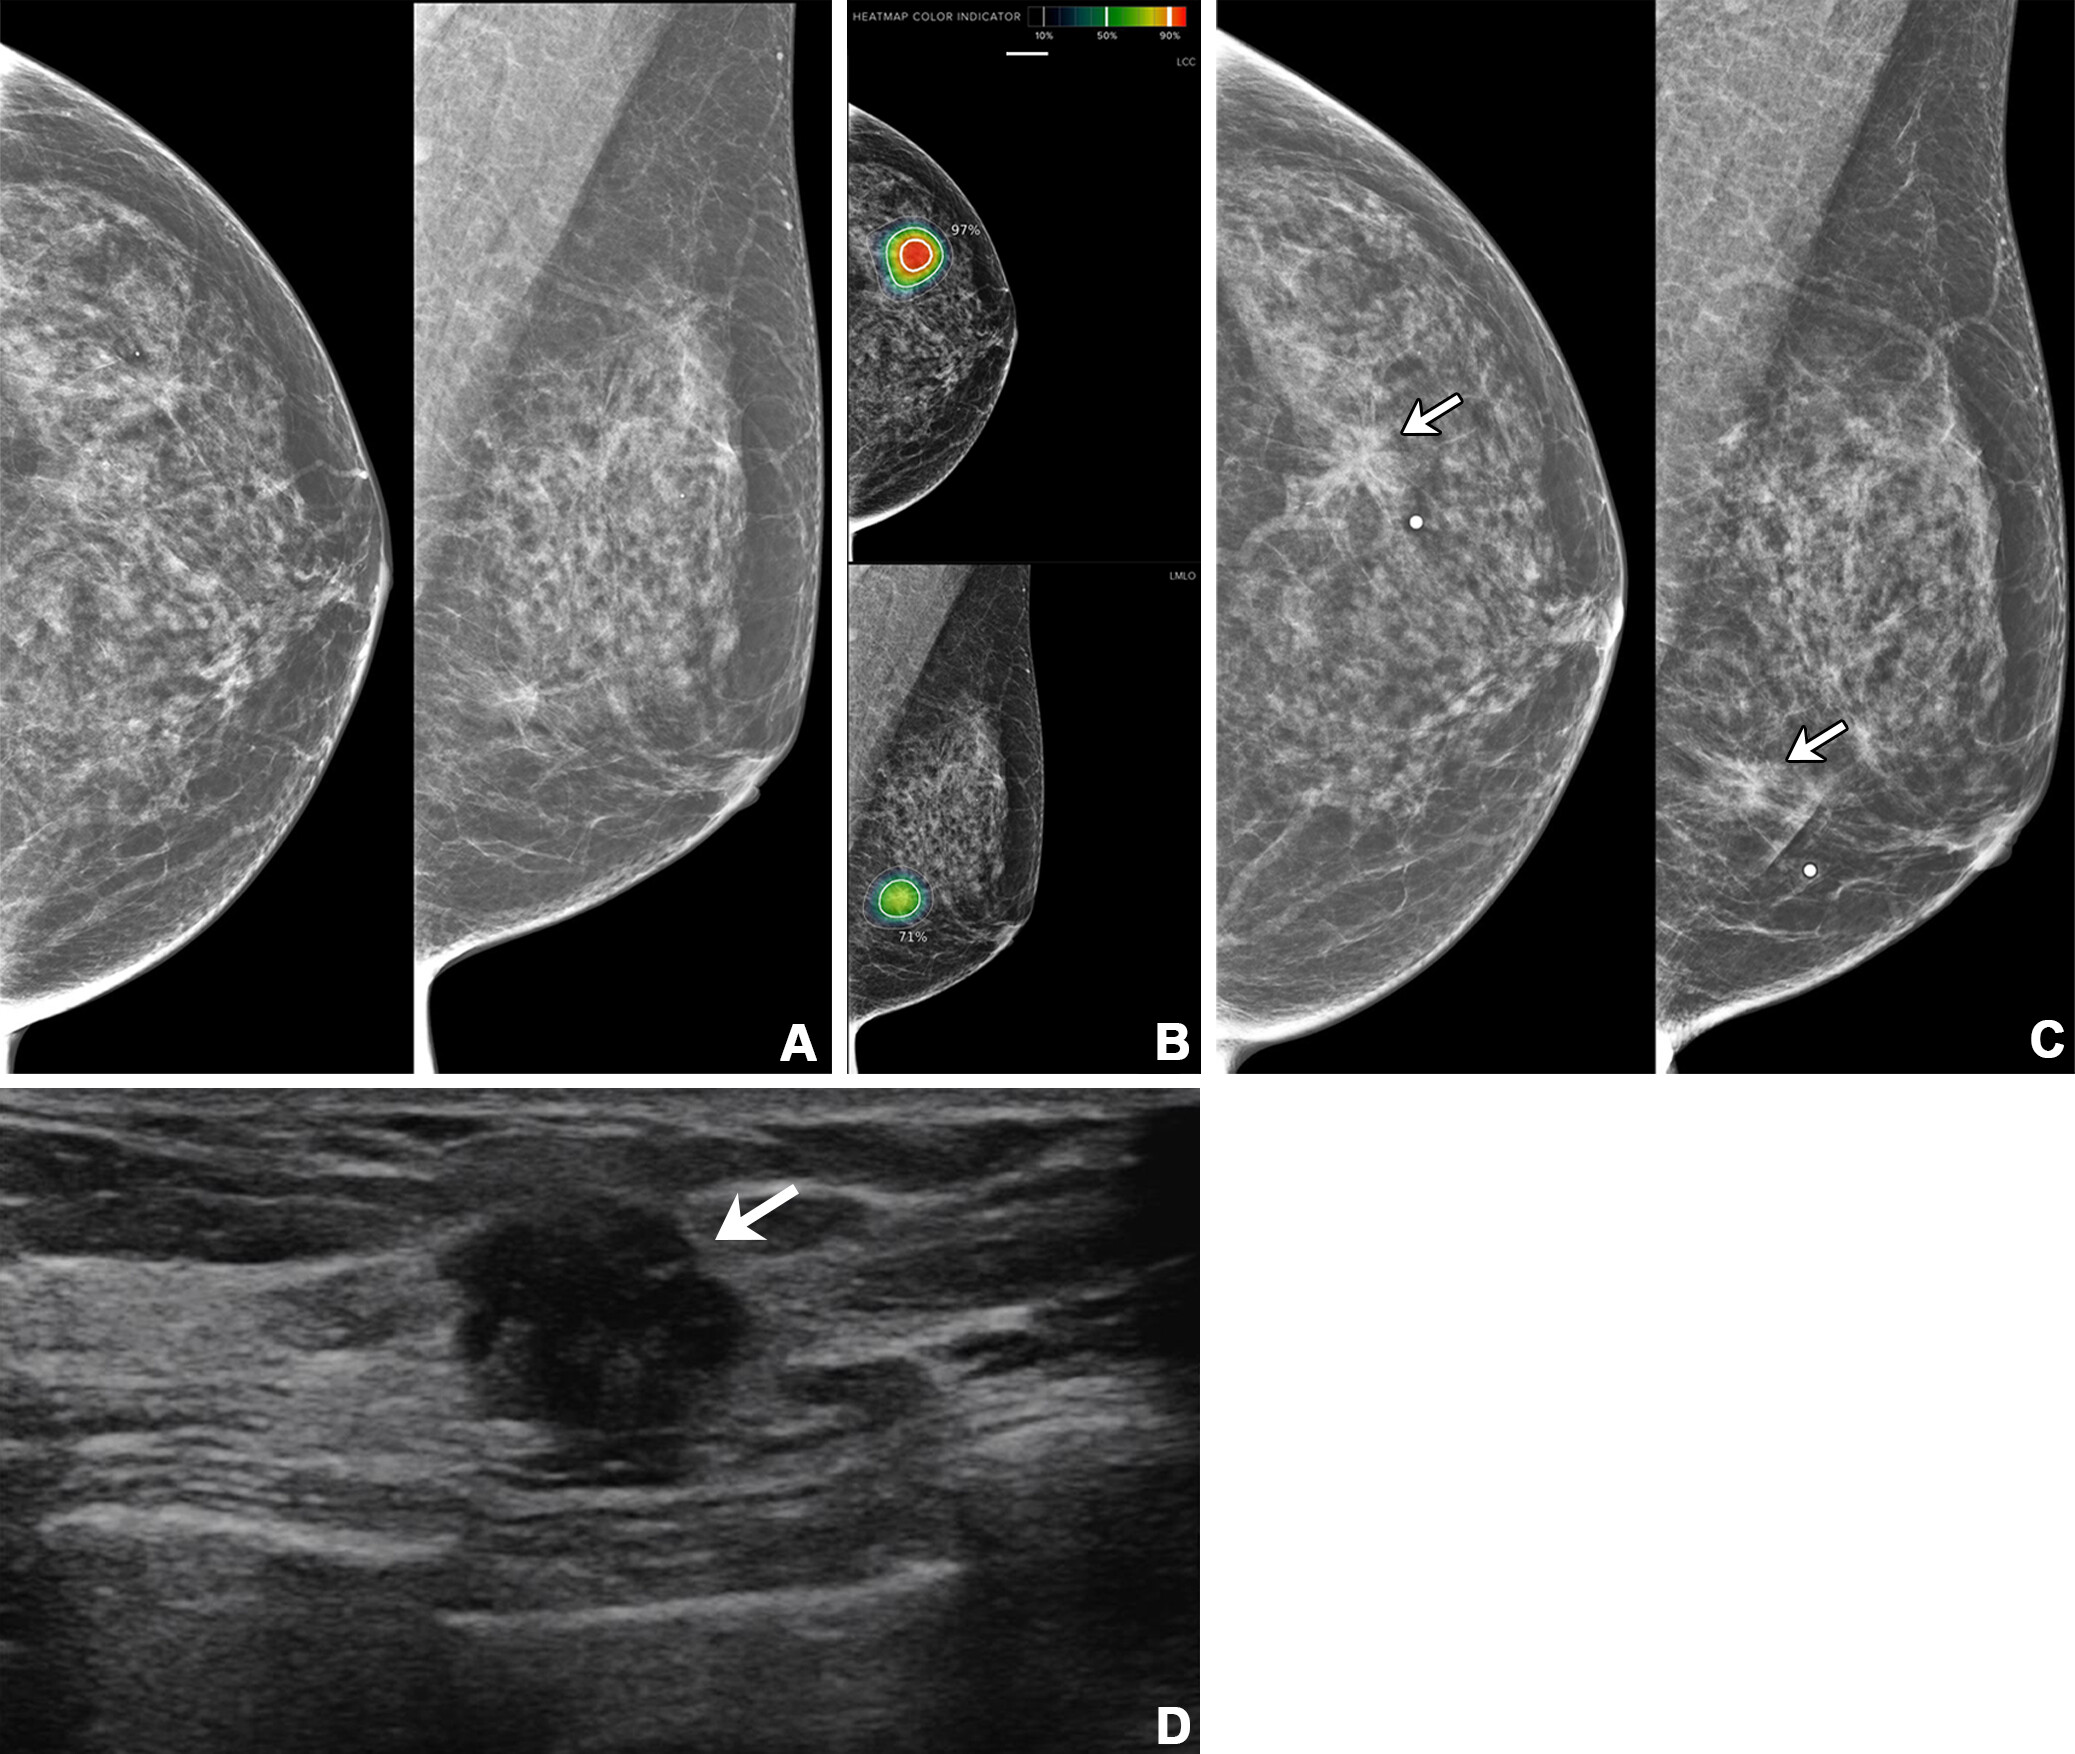

MBTST was a prospective, population-based paired study conducted between 2010 and 2015 that assessed the sensitivity and specificity of one-view DBT compared with two-view digital mammography in breast cancer screening. Findings indicated that DBT had a higher cancer detection rate, but more recalls than mammography.

Jögi and fellow researchers studied how DBT adds to early breast cancer detection. They assessed cancer detection rates, including the fraction of invasive cancers and cancer subtypes in consecutive routine digital mammography. The team analyzed two follow-up screening rounds: the first round was performed 18 to 24 months after the MBTST, and the second round was performed 36 to 48 months after the trial.

Cancer detection rates in MBTST were 6.5 (out of 1,000 women) for digital mammography and 8.7 for DBT. Also, the proportion of invasive cancers was 84.9%.